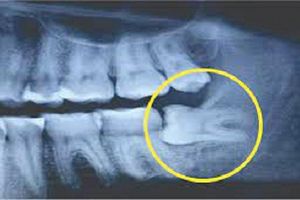

Sau khi có kết quả chụp X-Quang, bác sĩ chẩn đoán do 1 răng khôn của Lin mọc ngầm và lệch nên mới dẫn đến tình trạng đau nhức. 3 chiếc răng khôn khác cũng bị ảnh hưởng.Bác sĩ đã chỉ định Lin nhổ răng khôn bằng phương pháp gây mê. Trong đó, cô có thể chọn gây tê cục bộ hoặc toàn thân trong khi phẫu thuật. Sau khi thảo luận với mẹ, cô Lin quyết định nhổ bỏ cả 4 chiếc răng khôn bằng cách gây mê toàn thân.Trước khi phẫu thuật, bác sĩ đã kiểm tra tiền sử bệnh tật và các dị ứng thuốc. Song mọi vấn đề của bệnh nhân đều bình thường.